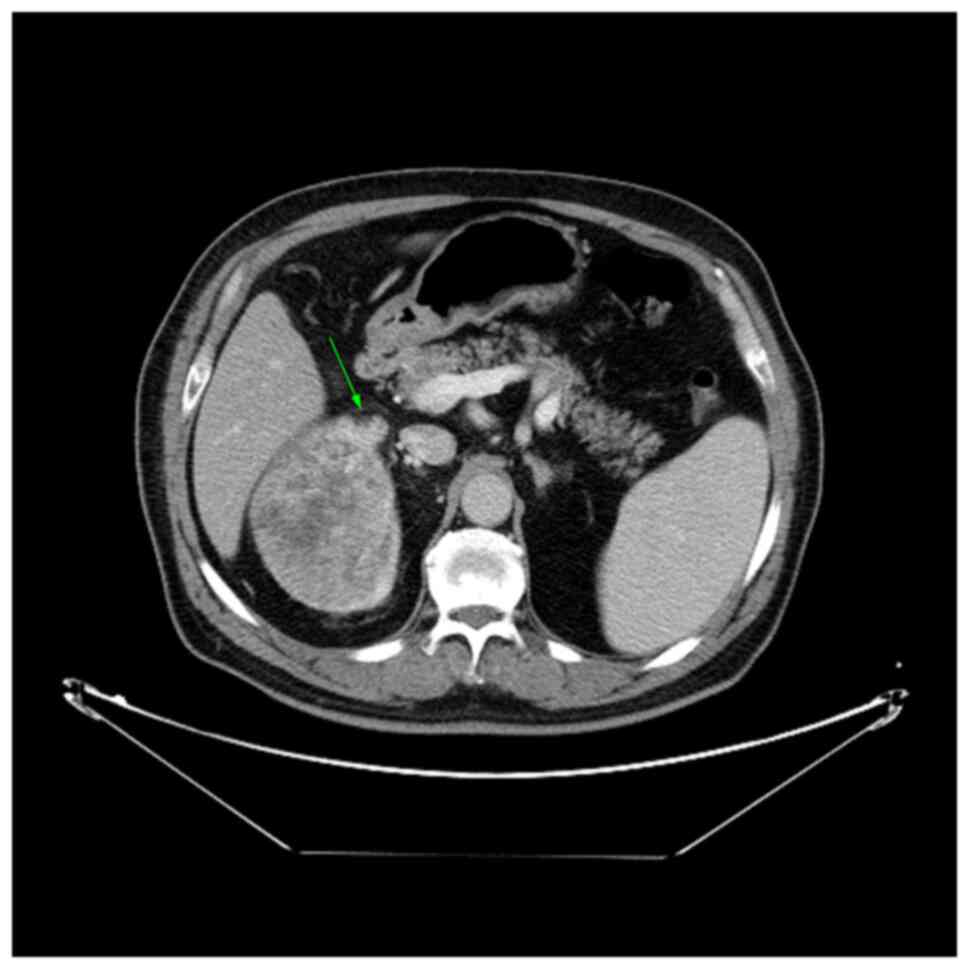

Fig. 2 demonstrates one of the criteria for perinephric fat invasion, namely, a nodular extension from the tumor to the perinephric fat (T3a). Fig. 3 shows an enhanced filling defect in the right main renal vein in the arterial and nephrographic phases without extension to the IVC.

Figure 3

Computed tomography scan of a right-sided RCC showing expansion and an enhancing filling defect in the right renal vein (stage T3a), as indicated by the arrow. The patient had von-Hippel-Lindau disease; there were two pancreatic lesions (serous cystadenomas) and a contralateral nephrectomy had been performed previously due to RCC. RCC, renal cell carcinoma.

Accurate preoperative assessment of invasion and the extent of tumor thrombi in the RV and IVC is essential for a surgeon to determine the right surgical strategy for thrombectomy and to reduce the risk of perioperative tumoral embolism (20). RV can be radiologically assessed for invasion when there is a hypodense filling defect that is continuous with the tumor or an extended RV with an intraluminal lesion, and the result becomes more specific when it is enhanced (10,21). Tumors can be classified as stage pT3a due to renal vein infiltration, renal sinus invasion or extracapsular extension, which can be small and thus difficult to detect on CT (2). In the study by Sokhi et al (10), a renal vein invasion with a specificity of 91-93%, but a sensitivity of 59-69%, was reported. Bradley et al (22) discovered renal vein involvement with a sensitivity and specificity of 84 and 98%, respectively. The sensitivity and specificity of the current study were 80 and 94%, respectively. Karlo et al (23) noted that the tumor edge touching the sinus fat was an accurate CT sign of branch RV invasion. Sokhi et al (10) also demonstrated that the presence of suspected sinus fat invasion, numerous perinephric septa, stranding or vascularity, and thickened perirenal fascia, especially in the case of a necrotic and irregular tumor edge, should alert the radiologist to perform a more proper examination of the renal veins.